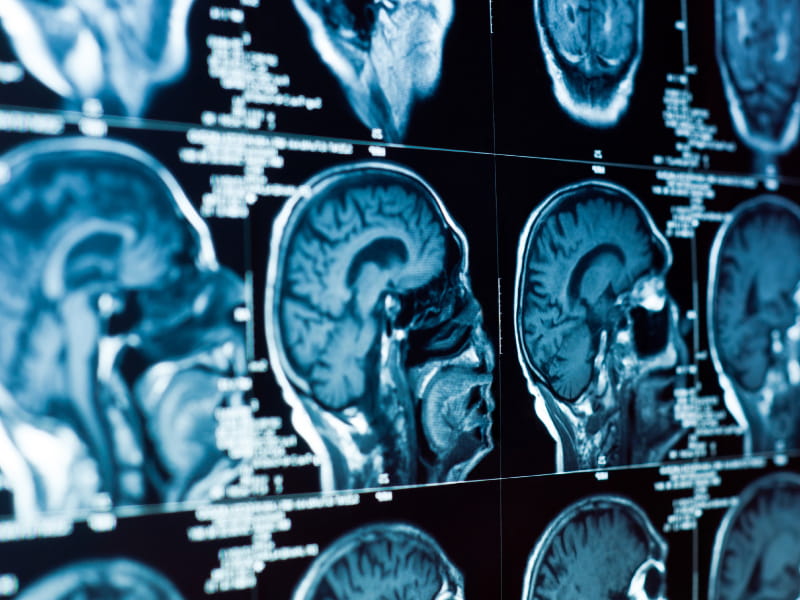

The new study, published Monday in the American Heart Association's journal Hypertension, focused on the blood pressure drug nilvadipine, a calcium channel blocker. Researchers randomly assigned 44 participants to receive either nilvadipine or a placebo for six months. Blood flow to specific regions of the brain was measured using a unique magnetic resonance imaging technique.

Results showed blood flow to the hippocampus – the brain's memory and learning center – increased by 20% among the nilvadipine group. Blood flow to other regions of the brain was unchanged.